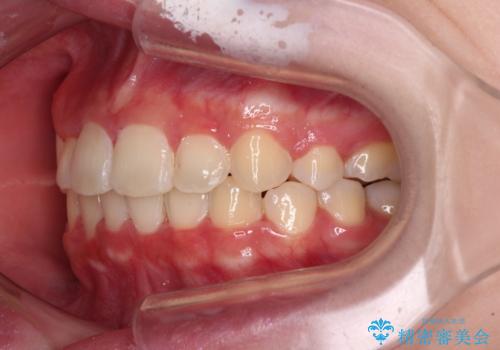

インビザラインが続けられない ワイヤー矯正での抜歯矯正 その2

- 八重歯やデコボコをインビザラインで治療したいとのことで来院された患者様です。

インビザライン単体で治療を行うには叢生が強いと判断されたため、事前にワイヤー装置で抜歯矯正を行い、ある程度改善してからインビザラインにて仕上げていくこととしました。